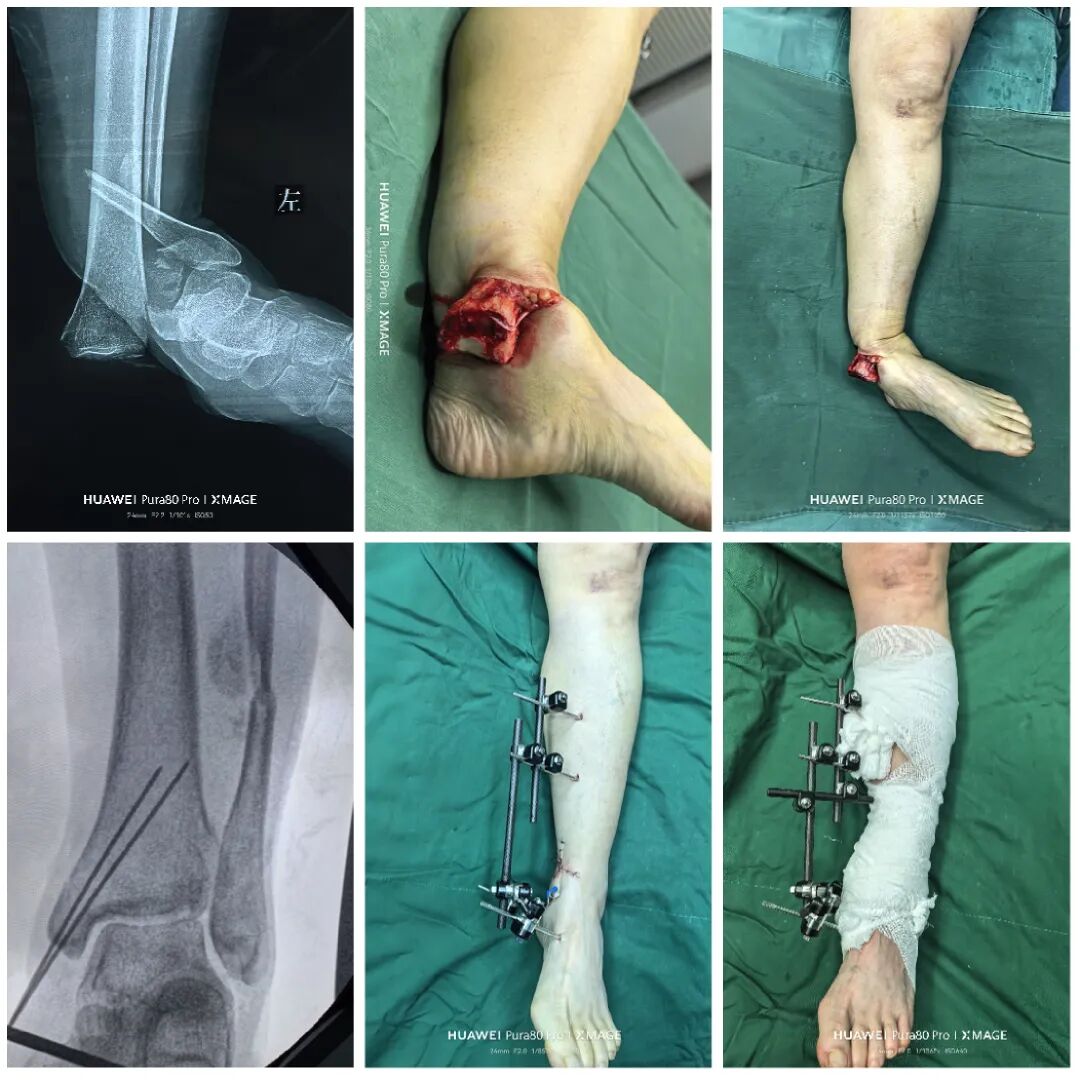

术后1周

内侧伤口愈合良好

行二次确定性手术

外架消毒

暂时不取

护皮膜封闭外架和内侧伤口

1,前侧小切口,复位Chaput骨块,3.5 mm空心钉垂直骨折线固定

2,腓骨粉碎,恢复长度即可,桥接固定,大蝶骨块用两个nice结捆于钢板

3,复位后踝

后踝有曲折